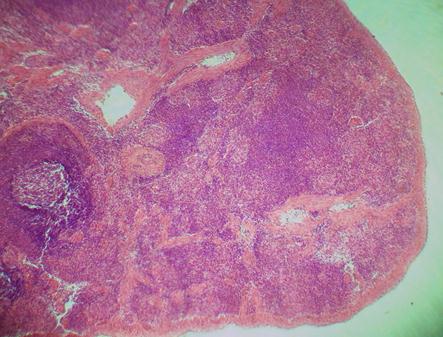

Фото 2.4.1. Селезенка. Гем.-Эоз.

Малое увеличение. (Ув.10х7)

При малом увеличении микроскопа:

б) найти капсулу селезенки и трабекулы. Капсула и трабекулы селезенки оксифильно окрашены.

в) найти белую пульпу(лимфоидные узелки селезенки). Лимфоидные фолликулы состоят, в основном, из мелких клеток темно-синего цвета.

г) найти красную пульпу(это светлые участки между лимфоидными узелками и трабекулами, состоящее из венозных синусов и селезеночных тяжей). Как правило, в этих участках большое количество эритроцитов желто-оранжевого цвета.

д) найти трабекуллярную вену. Вена обычно неправильной формы, стенка ее сращена с соединительной тканью трабекулы. Гладкие миоциты трабекулы расположены вдоль трабекулы.

е) найти трабекулярную артерию. Артерия имеет выраженную мышечную оболочку, состоящую из оксифильных гладких миоцитов, расположенных циркулярно.